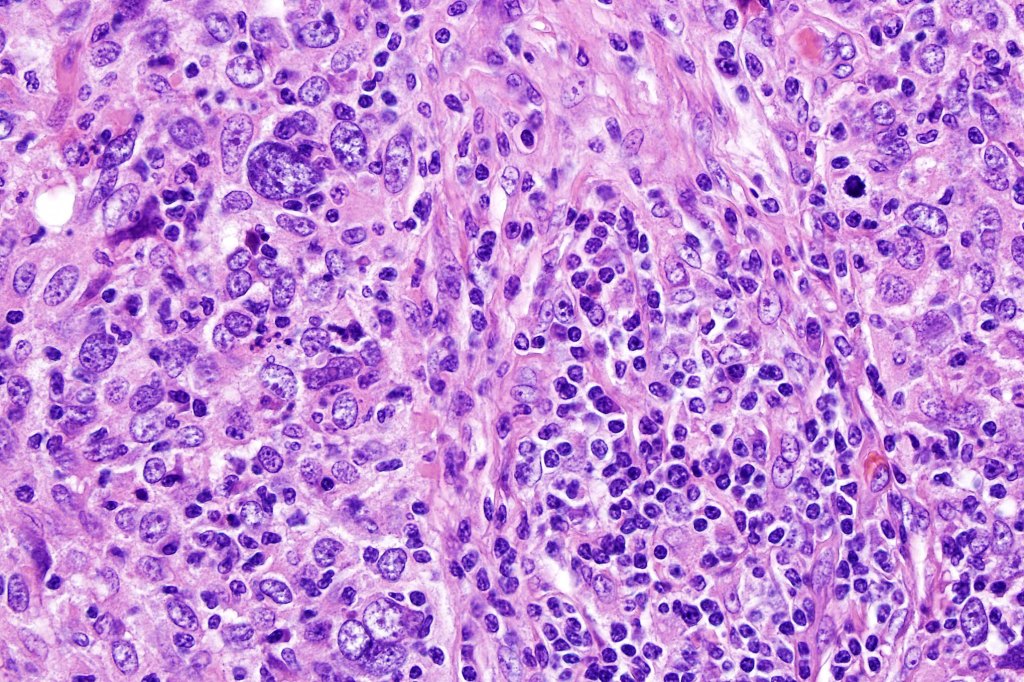

•Syncytial epithelial component in nests, cords or sheets surrounded by an intense lymphoplasmacytic infiltrate

•Epithelial cells are large with abundant cytoplasm and vesicular nuclei with conspicuous nucleoli

•Marked mitotic activity, variable pleomorphism